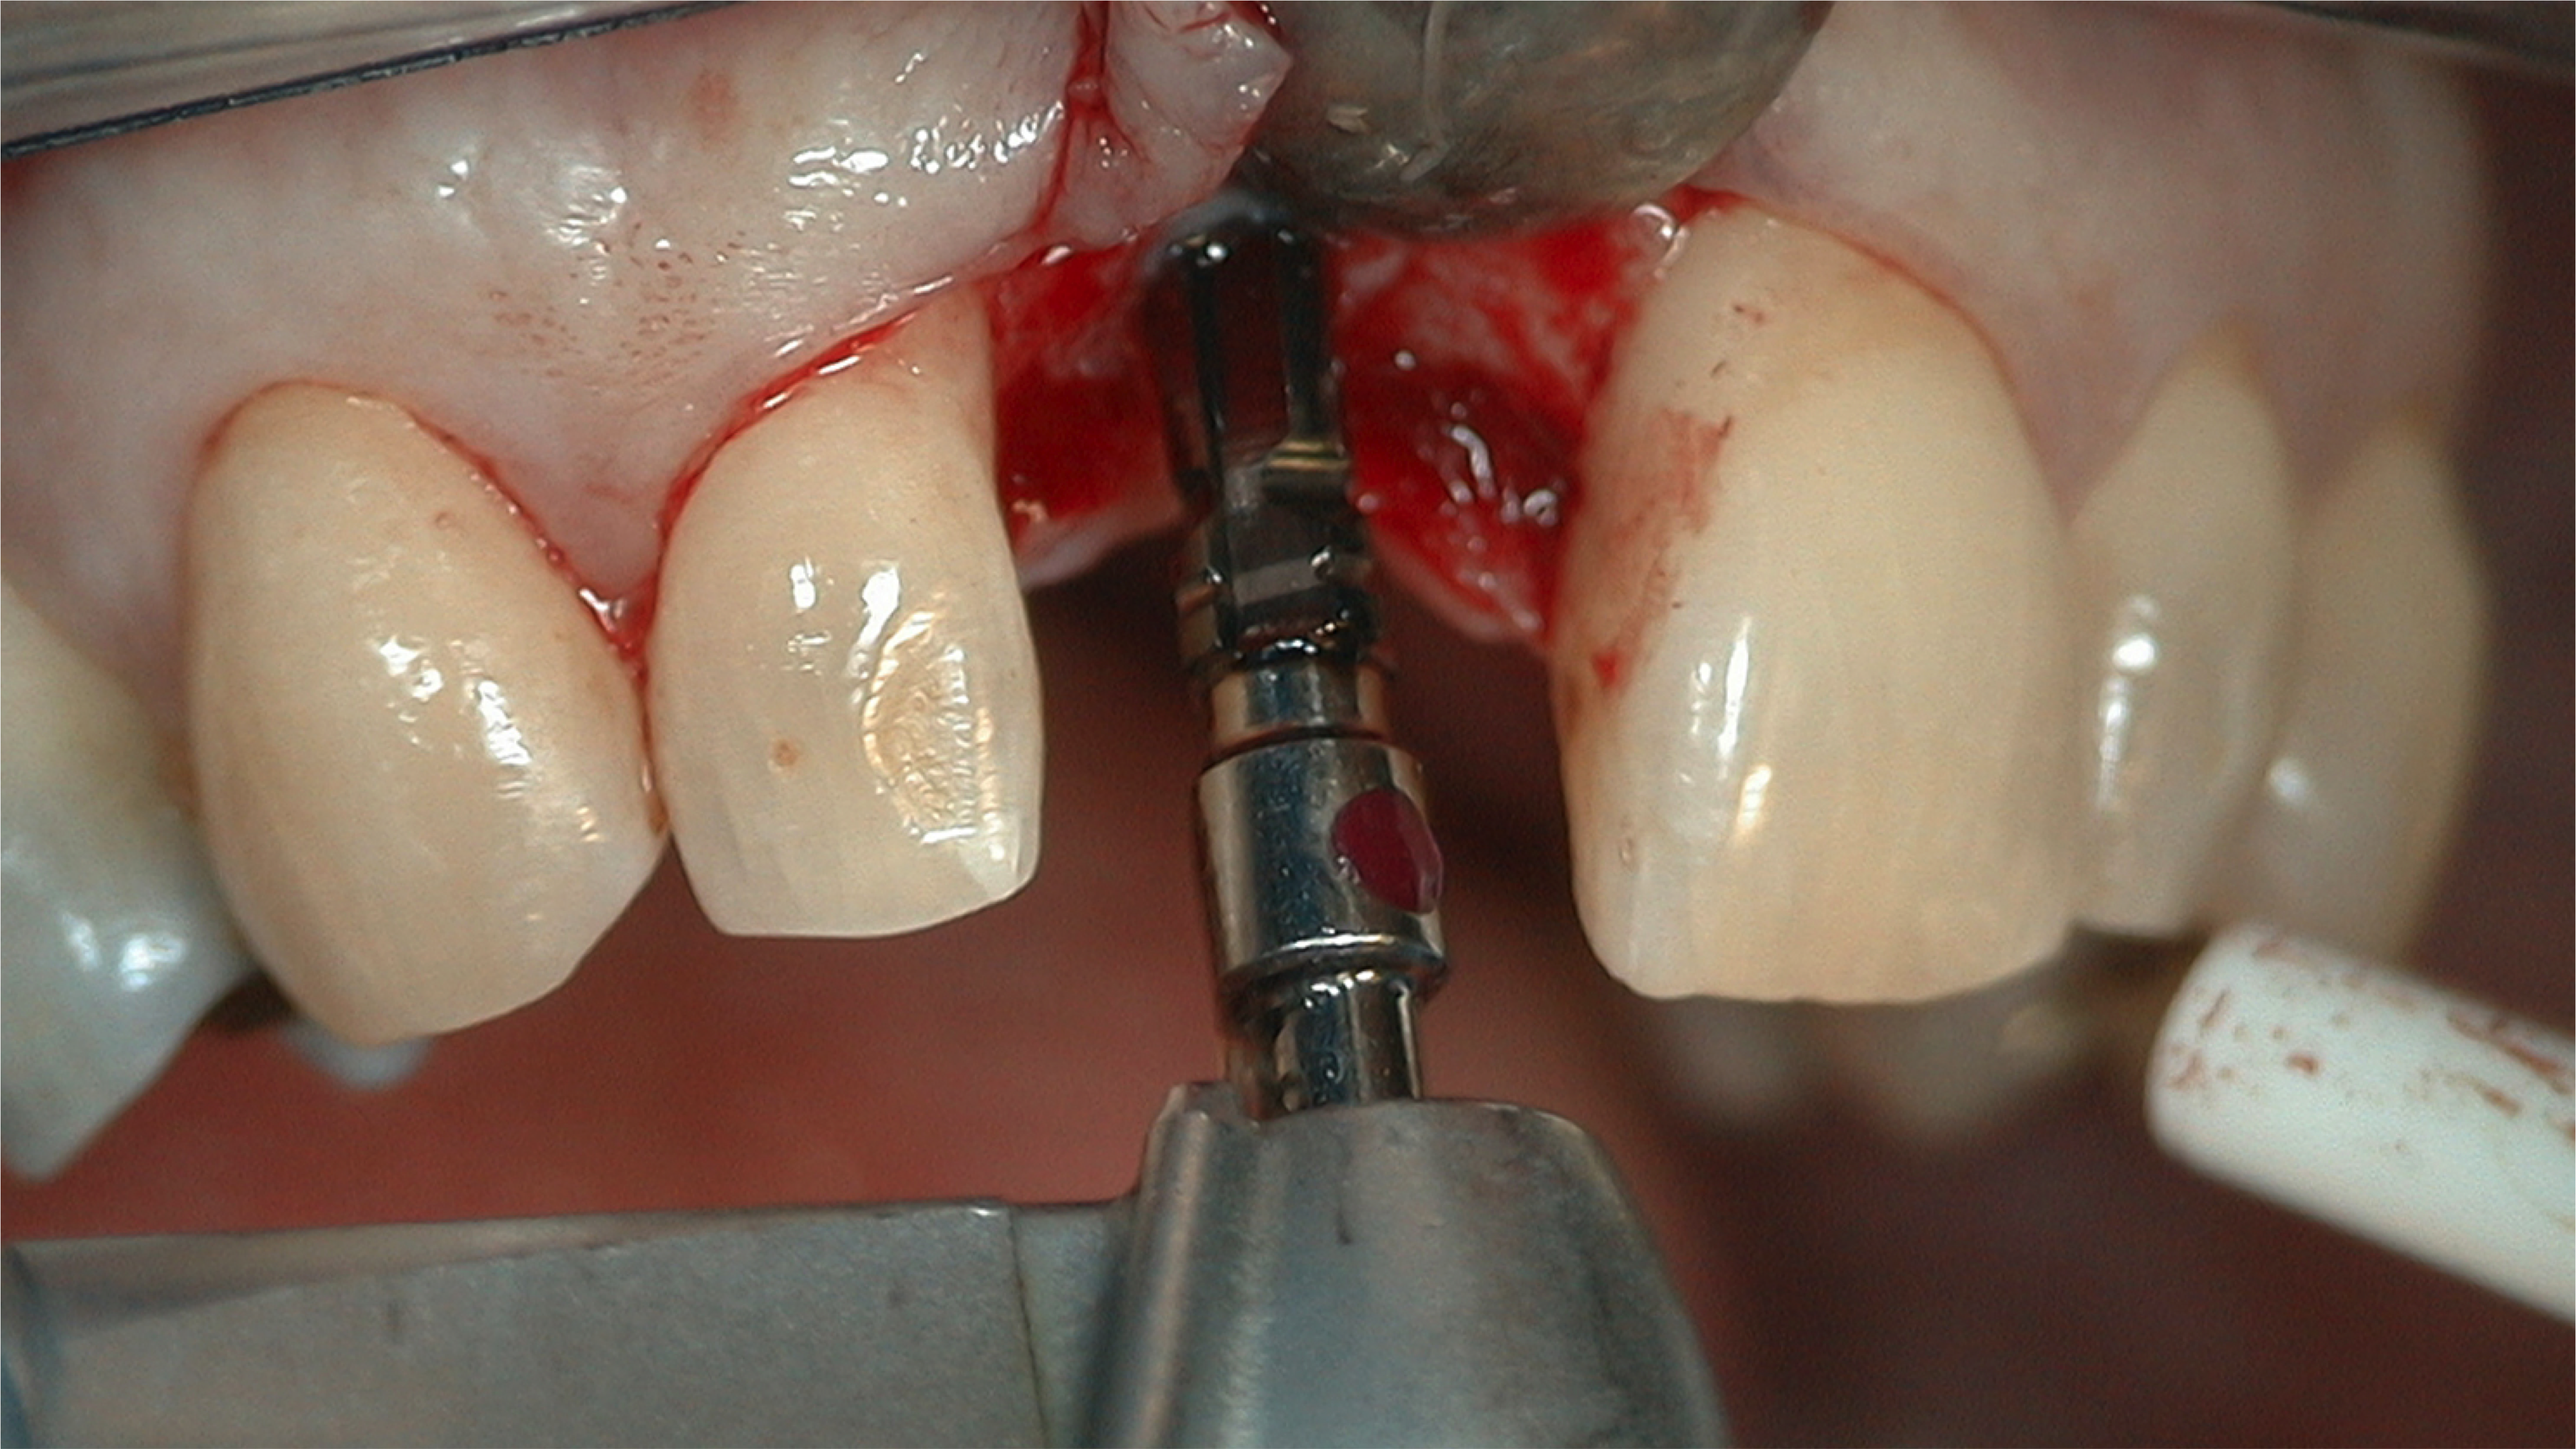

Fig 10. The osteotomy was initially 3.5 mm wide and taken to a depth of 11 mm. Note the red dot on the color-coded 3.5-mm drill.

Figure 10

Fig 11. A different drill was then used to widen and deepen the osteotomy to accommodate the selected implant. Note the yellow dot on the 4.3-mm drill.

Figure 11

Osteotomy and Implant Insertion

Different implants require the use of different drill kits for widening the osteotomy when going to depth. In the present case, the osteotomy is initially widened to 3.5 mm and taken to a depth of 11 mm (Figure 10), after which a different drill will be used to widen it to 4.3 mm and increase the depth to 13 mm to accommodate the selected implant (Figure 11).7 The implant is then inserted and properly torqued to 35 Ncm, after which a healing abutment is placed (Figure 12).